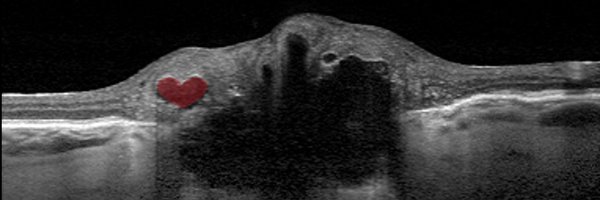

Excellent talk by @DanMilea3 on the discrimination between #opticdiscdrusen and #papilledema using #AI #EUNOS2022

Hamid Ahmadi, Steffen Hamann, and @MiriamKolko have published a new article on the importance of using enhanced depth imaging OCT (EDI-OCT) to improve diagnosis in glaucoma-related optic nerve head damage. You can read more here: https://t.co/JYf7W6o7Wf

An 83-year-old woman with a long history of glaucoma and optic disc drusen (ODD) was referred for neuro-ophthalmological second opinion. The patient had been treated for decades with bilateral...